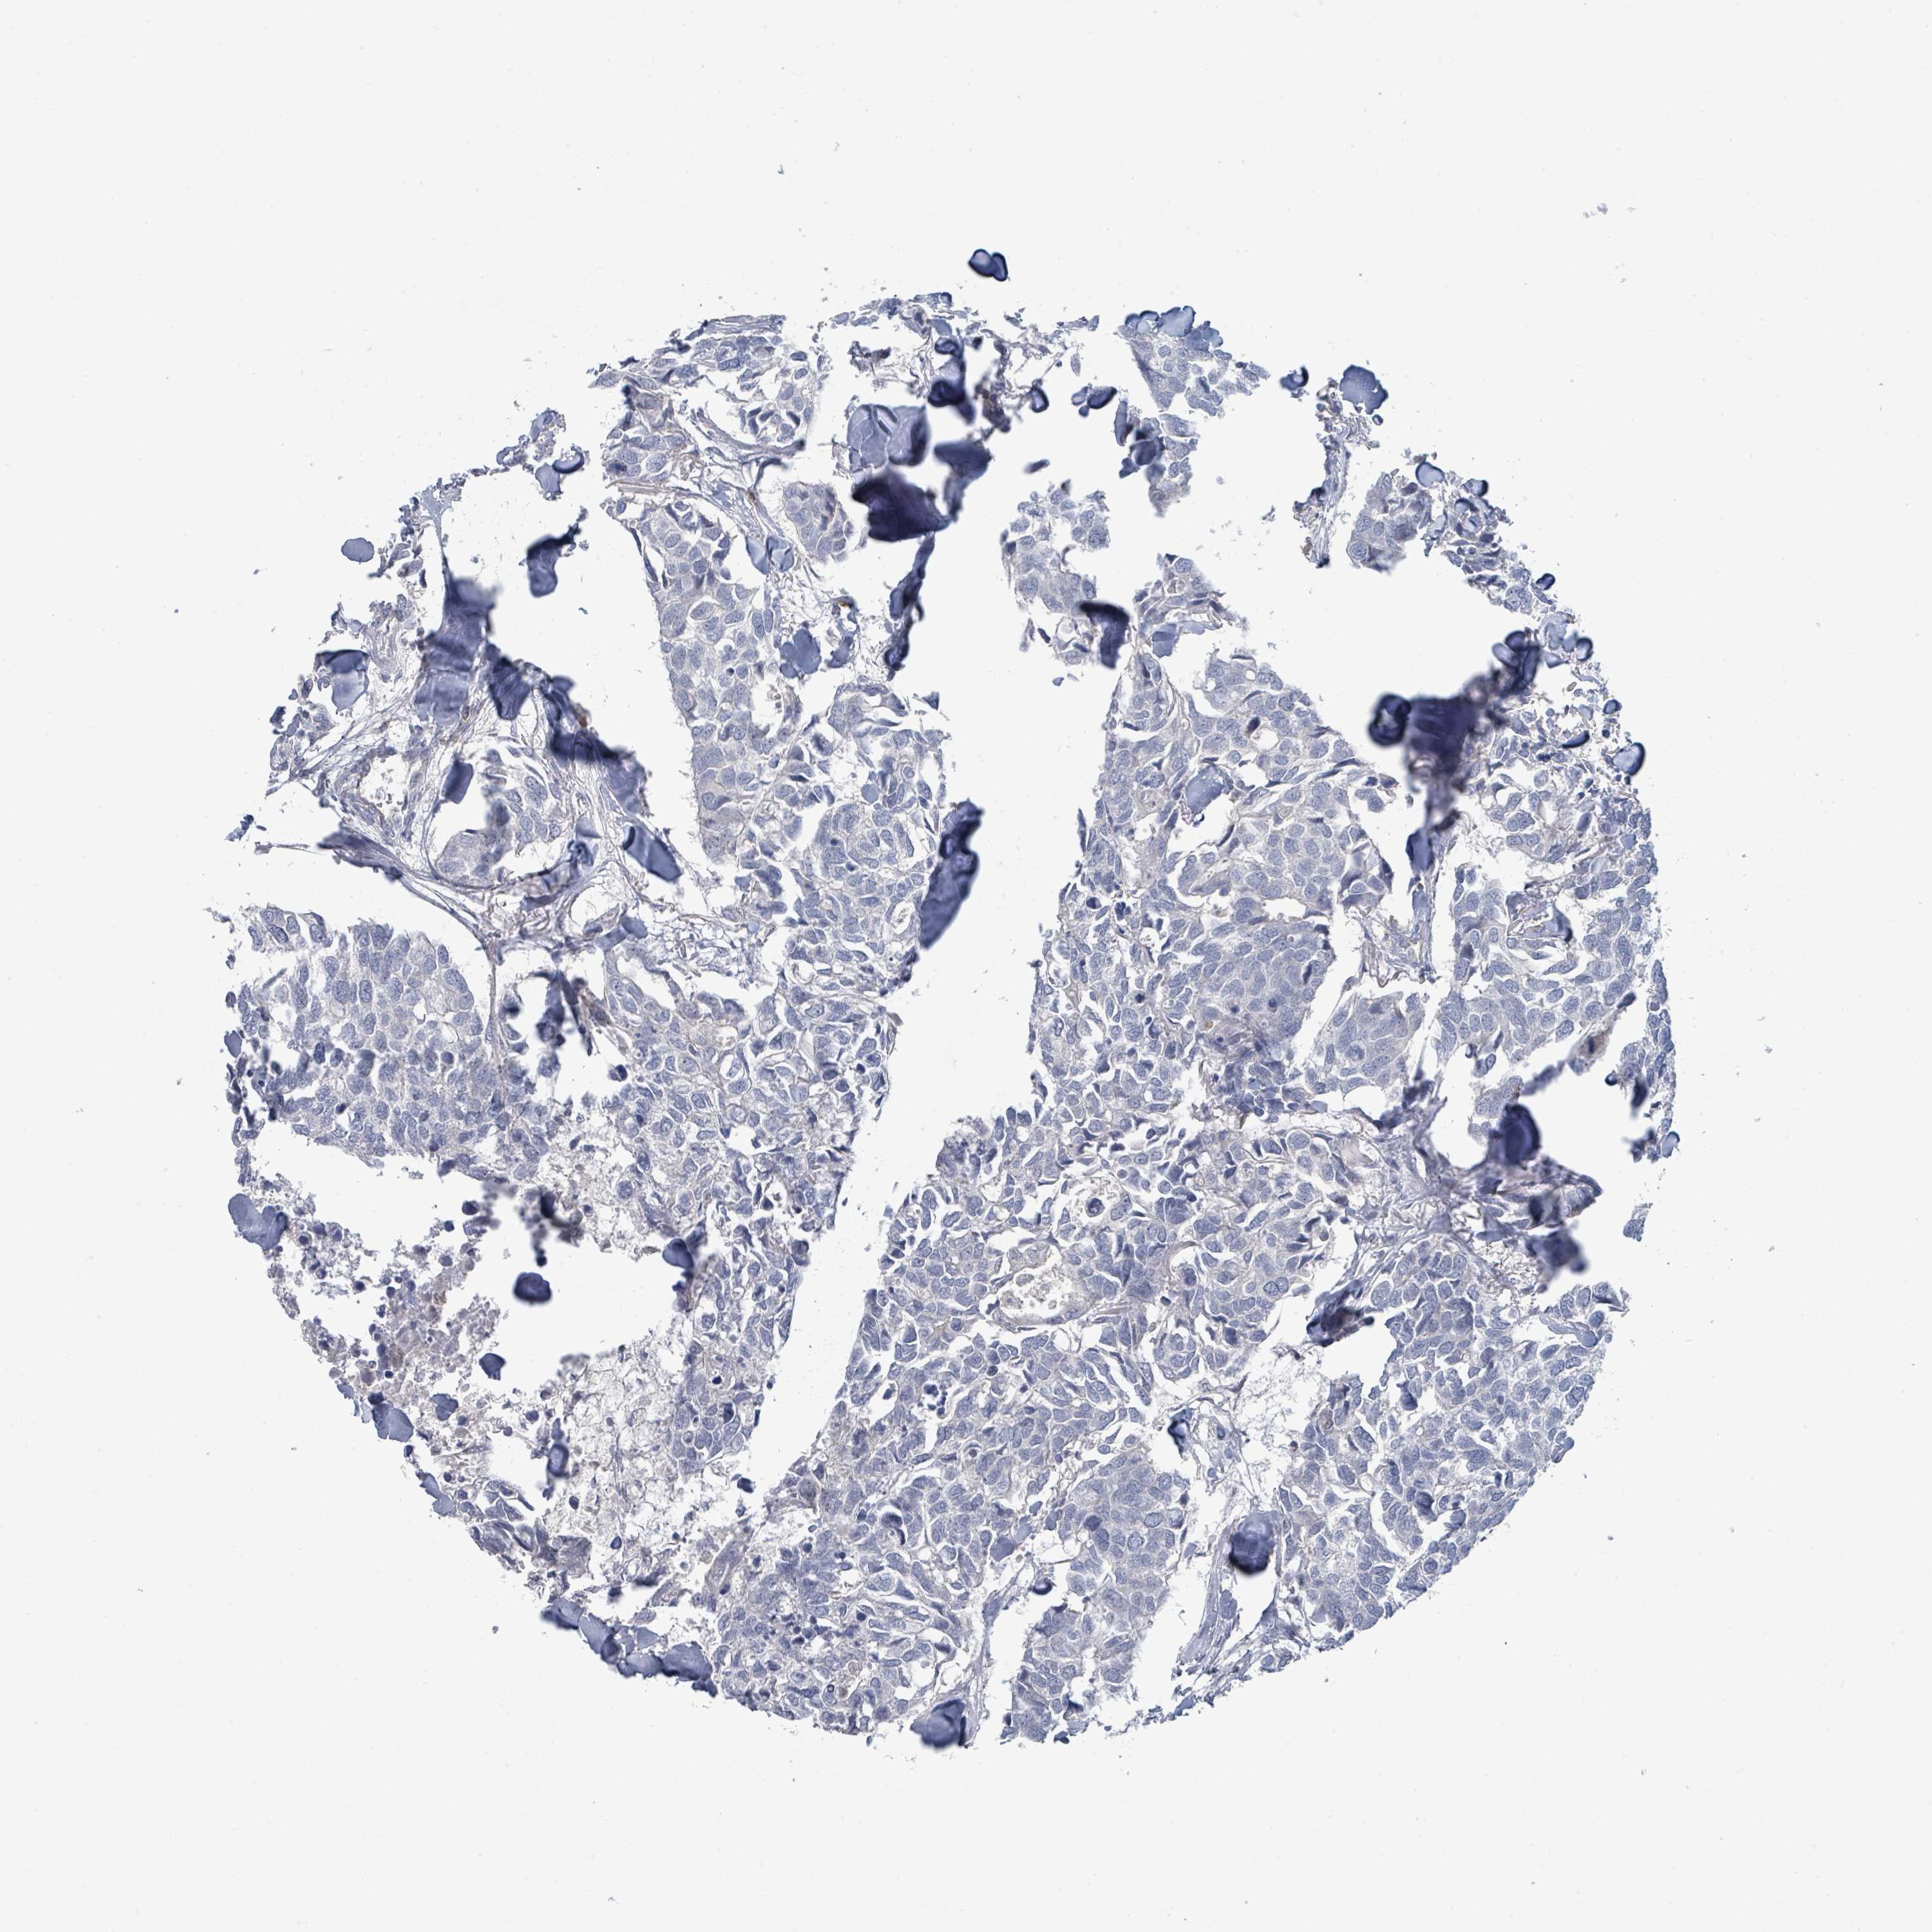

BRCA TCGA BRCA VALIDATION PROTEIN EXPRESSION

ANTIBODIES

AND

VALIDATION